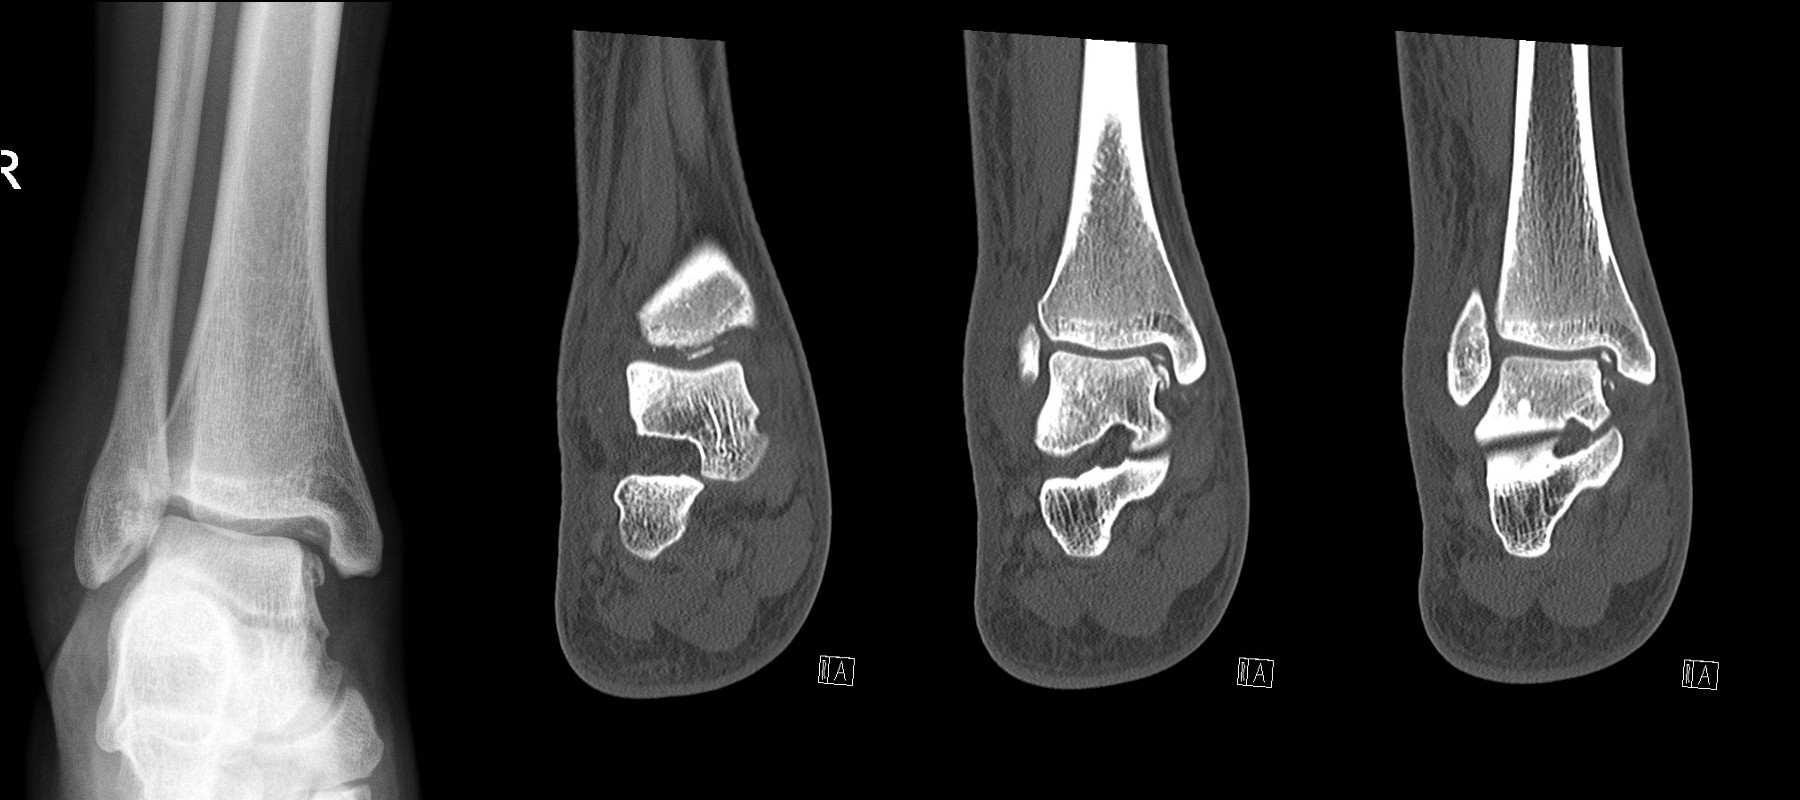

- A Computerised Tomography (CT) scan may be indicated in talar fractures, intra-articular calcaneal fractures, severe crush injuries or suspicion of Lisfranc injury.

Intra-articular calcaneal fractures

- Refer to the Orthopaedic team

Fracture of neck of talus

Talar dome fracture – looks simple on plain X-ray but CT shows multiple intra-articular bony fragments.